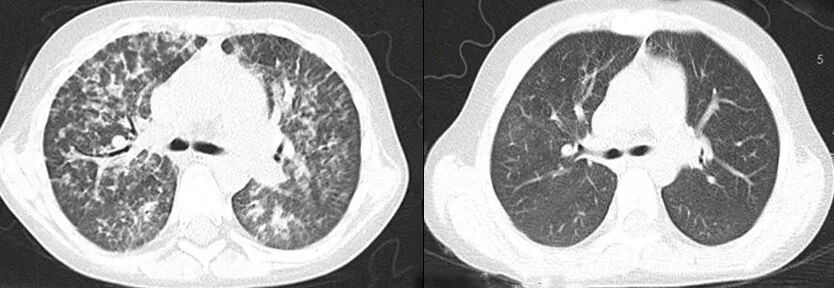

2019年,童童病情再次反复,出现了持续高热、持续咳嗽、肝脾肿大、全血细胞减少等新症状。肺部CT显示广泛的磨玻璃样病变。结合新症状和相关化验结果,协和儿科作出“噬血细胞综合征+肺泡蛋白沉积症”的诊断。

▲童童术前(左侧)和术后(右侧)的CT对比,肺泡蛋白沉积症状显著改善

移植后,童童回到协和儿科随访,变化令人欣喜。噬血细胞综合征表现迅速缓解,系统性红斑狼疮和肺泡蛋白沉积症的症状显著改善,肝脾明显缩小,代谢、免疫方面各项指标陆续从增高上百倍恢复到正常水平。